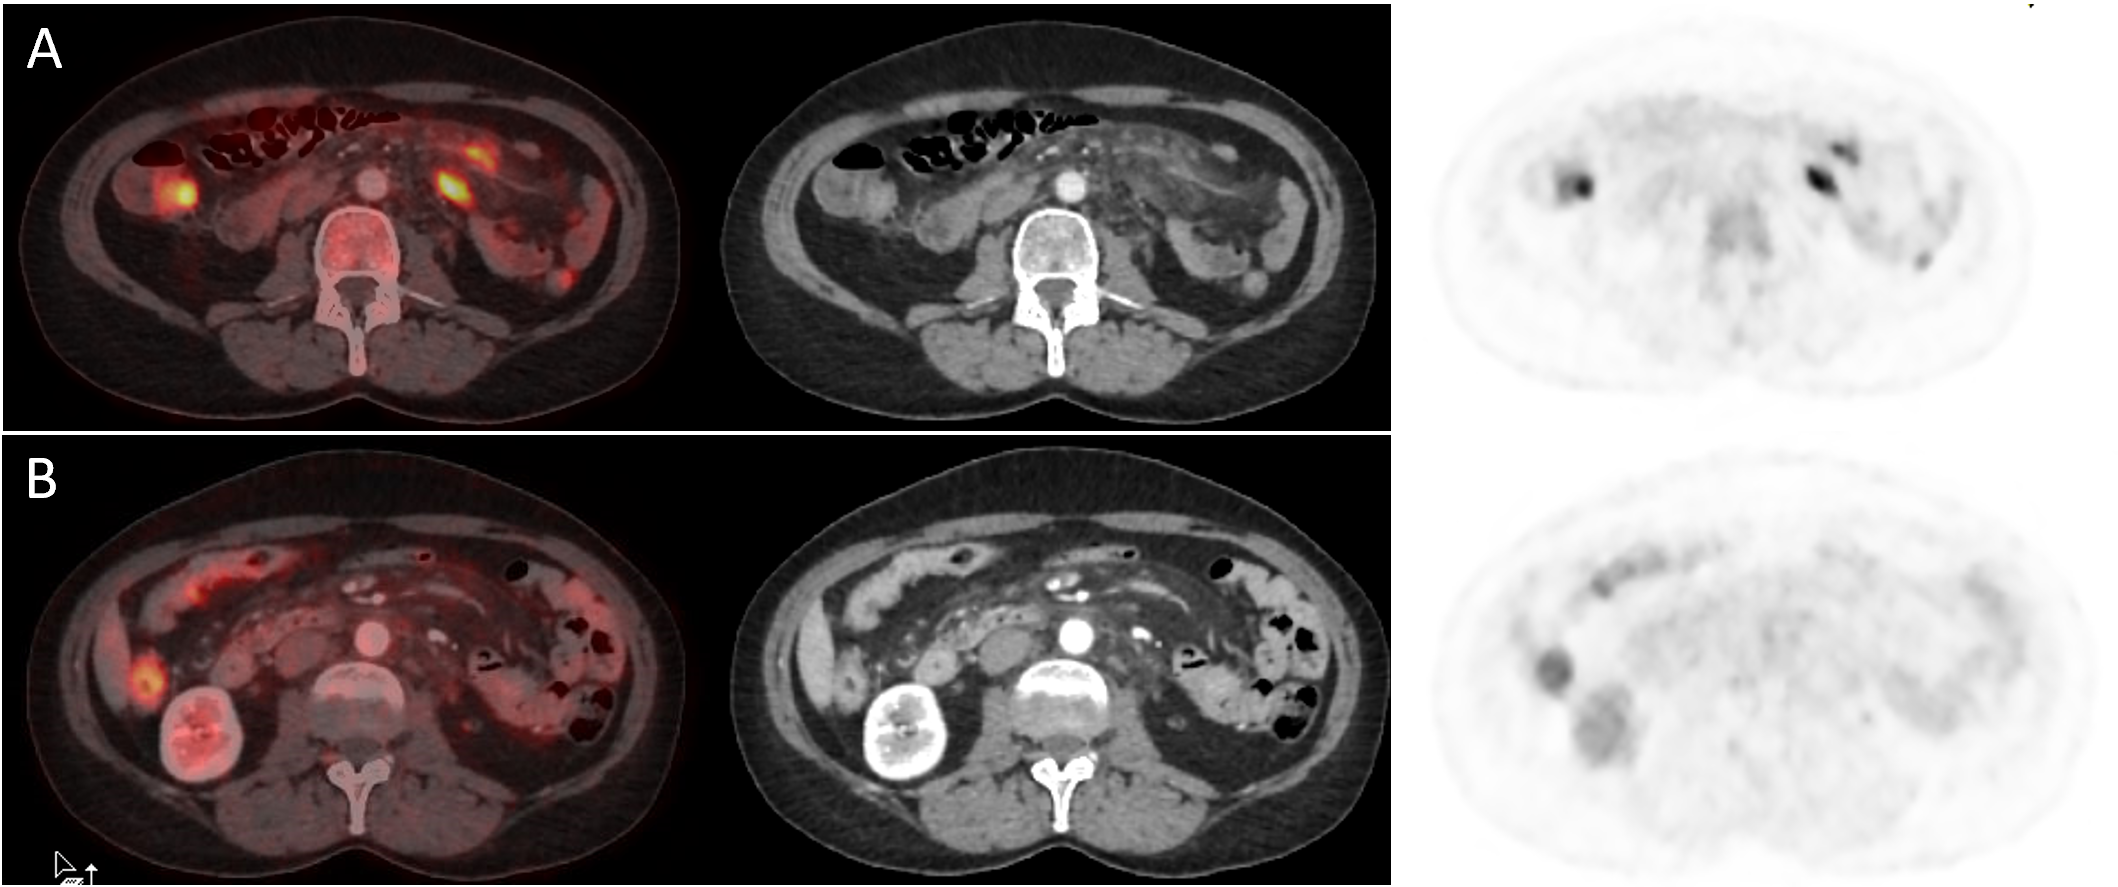

Figure 1 A 55-year-old female patient diagnosed in 2016 with grade 1 Follicular Lymphoma, stage IV in complete metabolic response (CMR) after treatment with chemotherapy (CT) until presenting relapse on PET/CT performed on 08/30/22 with involvement supra and infra diaphragmatic lymphatics, pleural and bone (A). The patient was included in a clinical trial for treatment with Epcoritamab + Lenalidomide + Rituximab with CMR in PET/CT controls performed in October 2022, December 2022 and January 2023 (B). Due to presenting neutropenia, was initiated a treatment with granulocyte colony-stimulating factor (G-CSF) on 02/22/23 for 5 days. Control PET/CT was performed on 02/23/23, observing complete metabolic regression of all the metastatic lesions seen in the baseline examination (persistence of CMR), with new lesions with intense accumulation of 18F-FDG in the mesenteric region (SUVmax: 7,2), suggestive of mesenteric panniculitis (MP), although relapse of the disease cannot be ruled out (C). The CT treatment continued without changes and a new control PET/CT was performed on 04/12/23 where persistence of CMR was observed with disappearance of the hypermetabolic mesenteric lesions (D). This suggests that it was a mesenteric panniculitis probably due to the use of G-CSF.